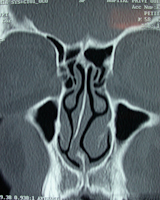

Scanner

Indispensável antes da rino-septoplastia e mesmo de certas rinoplastias, procura a sinusite (tratamento pré-operatório ou informação), uma anomalia congénita, estuda a deformação septal, o volume dos cornetos inferiores, a horizontalidade do pavimento e, por fim, traça objetivamente a deformação e a proporção da deformação óssea e cartilaginosa (que pode influenciar a decisão de realizar osteotomias).

Desvio importante do septo ósseo e cartilaginoso

Assimetria do pavimento da cavidade nasal   desvio de septo associado a grandes cornetos inferiores

- permite analisar o scan facial, caso tenha sido efectuado, e pode justificar procedimentos complementares nos seios nasais (meatotomia), nos cornetos inferiores (turbinoplastia por laser ou radiofrequência), no septo nasal (septoplastia, por vezes endoscópica), no queixo (genioplastia) , ver procedimentos associados.

Septo desviado direito

Corneto inferior esquerdo

sinusite maxilar bilateral, desvio do septo e

e perfuração do septo